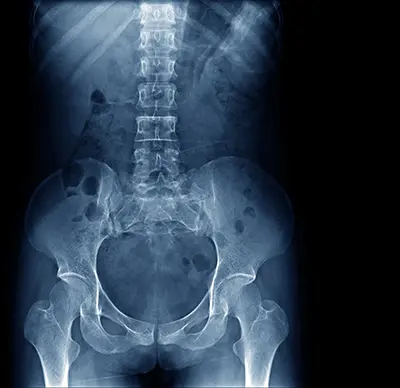

Diagnosing a core muscle injury involves a thorough review of symptoms, medical history, and a physical examination. Imaging may be used to confirm the diagnosis:

- X-rays: Can detect fractures or injuries to the pelvic bones